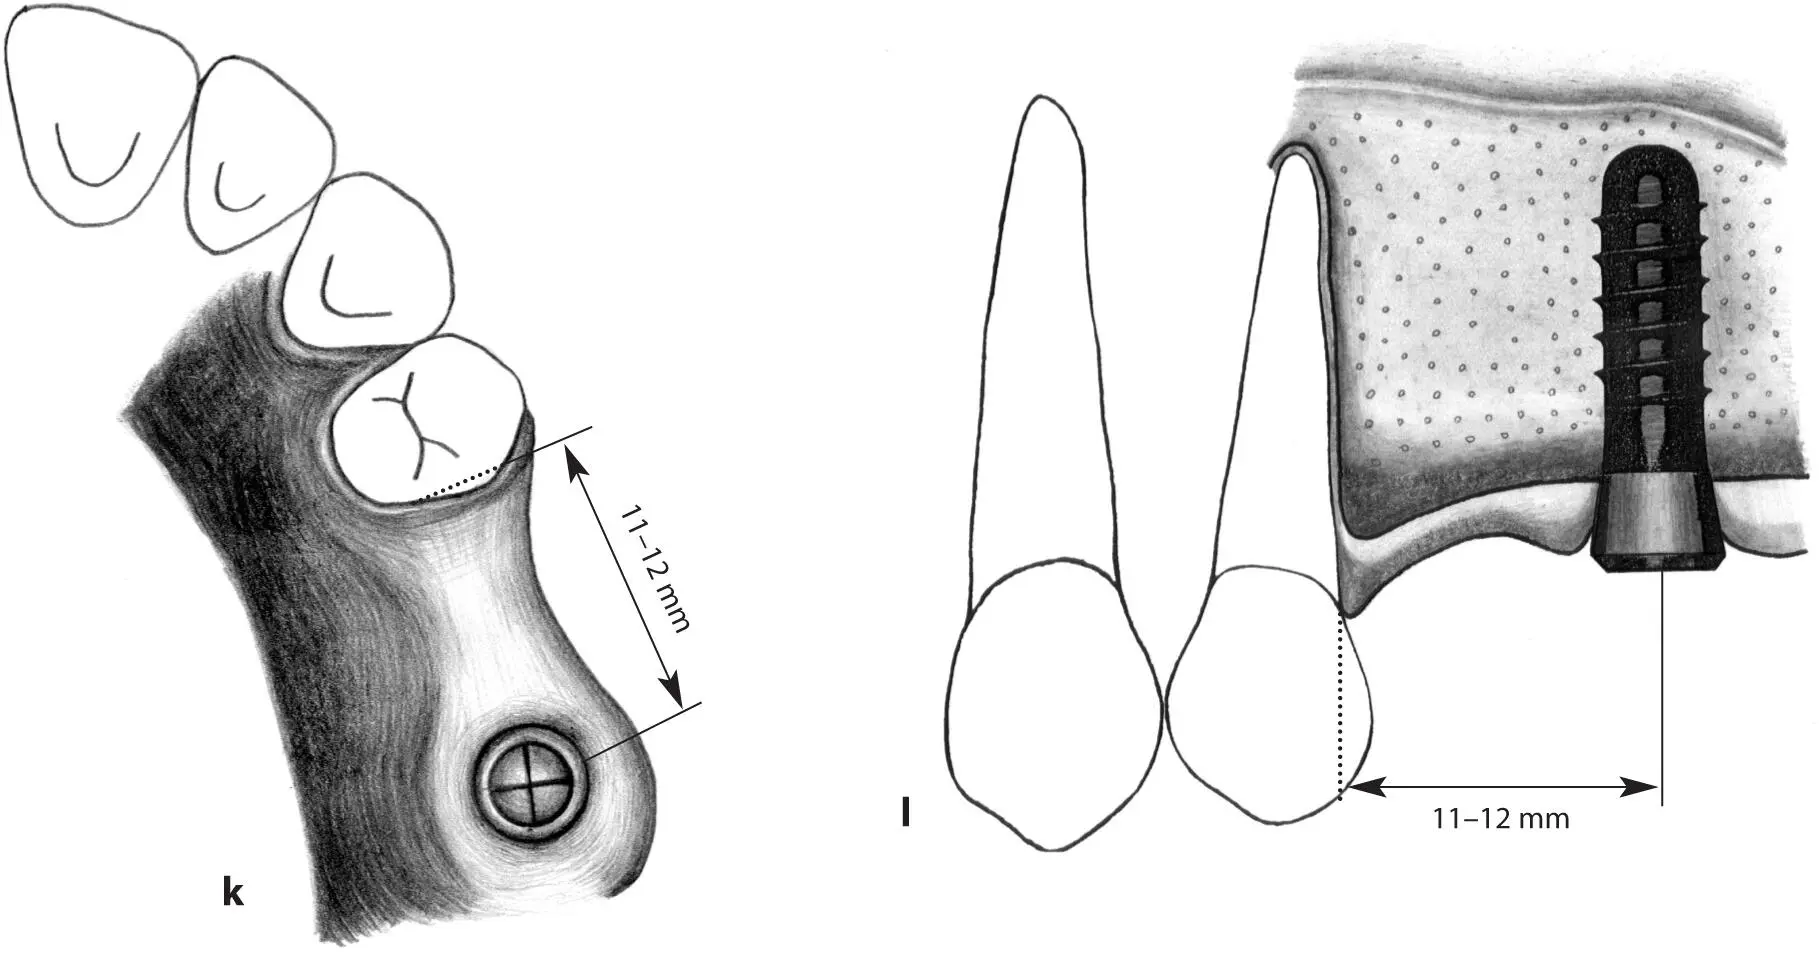

Figs 1-11k and 1-11l Occlusal (k) and lateral (l) views of a short distal extension situation. A regular neck implant is indicated to restore the missing first molar and serve as a distal abutment to a combined tooth- and implant-supported three-unit fixed partial denture. The implant is positioned 11 to 12 mm from the tooth.